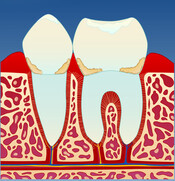

Gingivitt er en betennelse i tannkjøttet (gingiva).

Mangelfullt renhold kan over tid føre til utvikling av gingivitt. Dette skyldes bakterier og mykt belegg (plakk) som blir liggende på tannen i kontakt med tannkjøttet (fig. II). Om man har mye tannstein, vil også dette kunne medvirke til utvikling av gingivitt. Gingivitt oppstår lettest mellom tennene og ellers der det er vanskelig å holde rent.